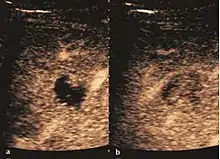

It is the most common liver tumor with a prevalence of 0.4 – 7.4%. It is generally asymptomatic but also can be associated with pain complaints or cytopenia and/or anemia when it is very bulky. It is unique or paucilocular. It can be associated with other types of benign liver tumors. Characteristic 2D ultrasound appearance is that of a very well defined lesion, with sizes of 2–3 cm or less, showing increased echogenity and, when located in contact with the diaphragm, a "mirror image" phenomenon can be seen. When palpating the liver with the transducer the hemangioma is compressible sending reverberations backwards. Doppler exploration reveals no circulatory signal due to very slow flow speed. CEUS investigation has real diagnosis value due to the typical behavior of progressive CA enhancement of the tumor from the periphery towards the center. The enhancement is slow, during several minutes, depending on the size of hemangioma and on the presence (or absence) of internal thrombosis. During late (sinusoidal) phase, if totally "filled" with CA, hemangioma appears isoechoic to the liver. Deviations from the above described behavior can occur in arterialized hemangiomas or those containing arterio-venous shunts. In these cases, differentiation from a malignant tumor is difficult and requires other imaging procedures, follow up and measurements of the tumor at short time intervals.[4]